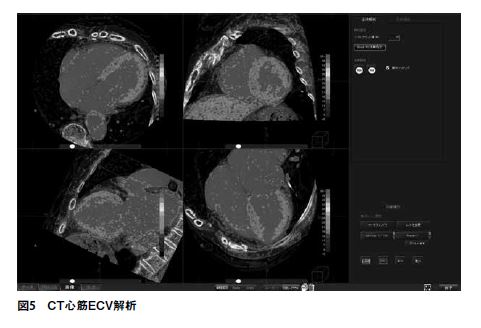

CT心筋ECV解析

最後にご紹介したいのが、「CT心筋ECV解析」である(図5)。CTにおける心筋ECV解析は最近のトピックであり、このアプリケーションも最新のアプリケーションである。ECV解析というのは、心筋における心筋線維化の程度を定量的に評価する手法であり、MRIでの評価がゴールドスタンダードである。しかしながら、近年では逐次近似再構成や様々な画質改善方法の登場によって、CTでも同等の解析が行えるようになった。CTによるECV解析には、シングルエネルギーによって、造影前後の画像(単純・遅延造影)をサブトラクションすることにより算出するサブトラクション法と、デュアルエネルギーによって、遅延造影のヨード密度画像から算出するヨード法がある。どちらの手法においても、従来はマニュアルでROIを囲い、値をエクセルシートなどで計算するという手順を踏む必要があった。このアプリケーションを使用すれば、計算を自動で行い、心筋全体のECV値を算出することが可能である。セグメントごとの表示も可能だ。またサブトラクション法では、非剛体位置合わせを使用するので、位置ずれの影響がない。そして、このアプリケーションを使うことにより、3次元ボリュームデータとしてECVマップを保存することが可能である。このデータと、冠動脈CTAの画像をマルチデータフュージョンさせれば、また新たな付加情報を得ることができる(図6)。まだ登場して間もないアプリケーションではあるが、こういった評価手法は、今後の心臓CT検査において欠かせないものとなっていくだろう。